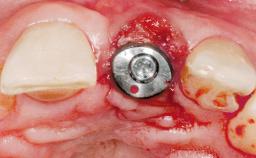

Immediate Placement of an Implant in a Maxillary Left Central Incisor Site

A 33-year-old female patient presented with an upper left central incisor that required extraction after a failed endodontic therapy. The tooth had been traumatized when the patient was a teenager and had undergone several endodontic treatments, including two apicectomy procedures. The patient was in good health and did not smoke. Clinical examination showed that the patient had a high lip line. In full smile, the gingival margins of the upper teeth were visible to the first molars. The gingival margins of central incisors 11 and 21 were only just showing. Examination of tooth 21 confirmed that the tooth was mobile and had hypererupted by 1 mm.

Soft Tissue Grafting Simultaneous

Placement Protocol Immediate implant placement

Tooth Site Maxillary incisor or canine

Socket Morphology Single-root socket

Socket Integrity Damage to one or more bone walls

Provisional Implant-Supported Prosthesis Prosthodontic margin > 3 mm apical to mucosal margin Prosthodontic margin > 3 mm apical to mucosal margin